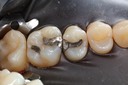

Mark Chun #17 prep